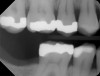

Fig 3. Patient No. 1, contralateral side; in 2009 patient presented with teeth Nos. 15 and 18. Subsequently, tooth No. 18 was extracted due to tooth fracture.

Figure 3

Fig 4. Patient No. 1 in 2016, with extrusion of tooth No. 15. Two different experiences in the same mouth, as shown in Figs 1–2 and Figs 3–4, underscore the unpredictability of extrusion.

Figure 4

Another consideration is mean vertical displacement of unhampered posterior teeth, which in some studies was minimal: 0.8 mm37 and 0.9 mm30 (Table 1). Yet, there could have been sites where the amount of extrusion was clinically relevant. When Lindskog-Stokland et al assessed the risk of over-eruption using 1 mm as a threshold, they stated there was an odds ratio of 3.3 that unimpeded molars would extrude 1 mm compared to opposed molars.30 Based on their calculations, however, it is unclear which patients with a missing molar are at risk of over-eruption (Figure 1 through Figure 4). Indeed, if susceptible individuals could be identified, then restorative therapy could be initiated to stabilize their occlusion (eg, tooth replacement). Furthermore, odds ratios can be highly misleading, and predictive values would provide clinicians a better perspective as to what percentage of sites may experience significant extrusion.41,42